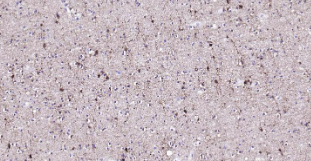

Immunohistochemical analysis of paraffin embedded human left parietal lobe tissue slide using IHC0219H (Human NMDAR1 IHC Kit).